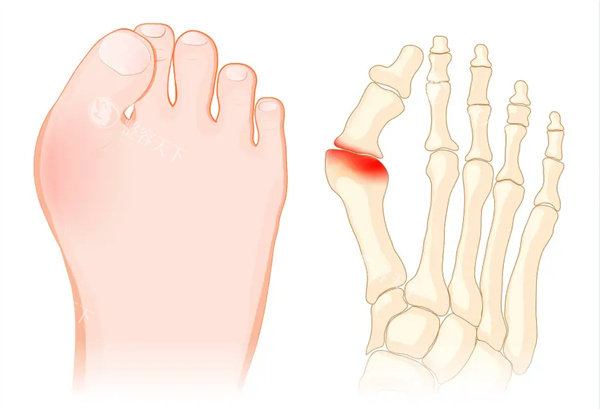

导读:“穿凉鞋像踩刀尖,高跟鞋一碰就疼得龇牙咧嘴!”北京32岁的李女士摸着脚上凸起的骨包,对着镜子叹气——这拇外翻的“大脚拐”,让她从时尚达人变成“拖鞋战士”。像她这样被拇外翻折

“穿凉鞋像踩刀尖,高跟鞋一碰就疼得龇牙咧嘴!”北京32岁的李女士摸着脚上凸起的骨包,对着镜子叹气——这拇外翻的“大脚拐”,让她从时尚达人变成“拖鞋战士”。像她这样被拇外翻折磨的人,国内超6000万!选医生时,李昕宇和温建民的名字总被反复提起,到底该翻谁的牌子?今天咱们就掰开揉碎唠清楚!

“李医生,我这脚歪了十年,还能救吗?”56岁的王阿姨攥着X光片,脚上第二脚趾已经翘得像“小锤子”。李昕宇推了推眼镜,指着片子:“拇外翻角45度,跖骨内收,得用三代Scarf截骨+Akin术式。”